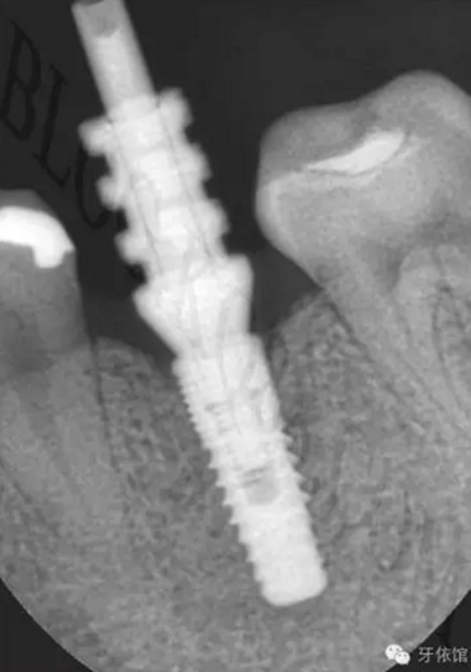

連接印模帽后拍x光片,檢查印模帽與種植體之間是否緊密相連。